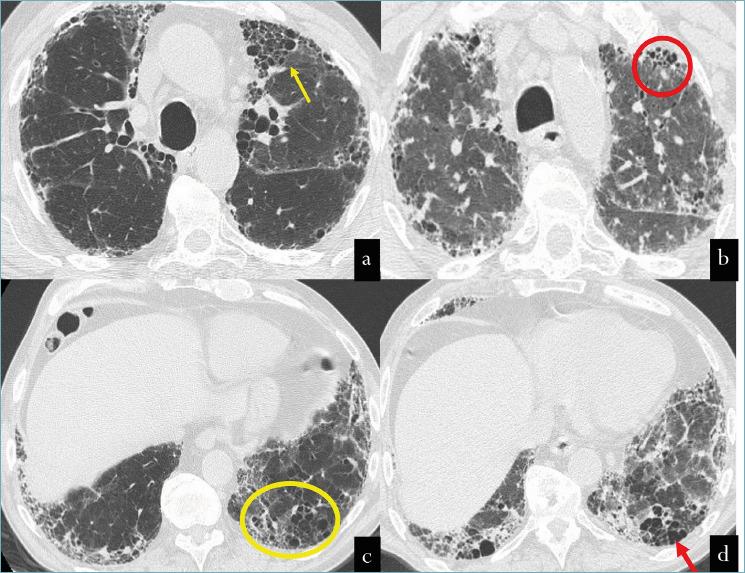

The pathogenesis of idiopathic pulmonary fibrosis: from "folies à deux" to "Culprit cell Trio".

Pathologica. 2025 Feb;117(1):3-9. doi: 10.32074/1591-951X-1123.